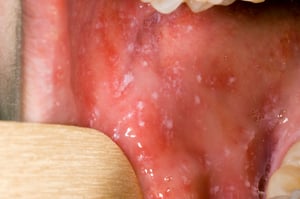

Avant le début de l’éruption cutanée, des taches de Koplik peuvent apparaître à l’intérieur de la bouche. Les taches de Koplik sont de petits boutons rouge vif avec un centre blanc ou blanc bleuté. Leur centre peut ressembler à un grain de sable.

Les taches de Koplik sont des boutons rouge vif avec un centre blanc ou blanc bleuté pouvant ressembler à des grains de sable. Elles peuvent toucher n’importe quelle région de la bouche chez les personnes qui ont la rougeole.

Image publiée avec l’aimable autorisation de la Public Health Image Library des Centers for Disease Control and Prevention.